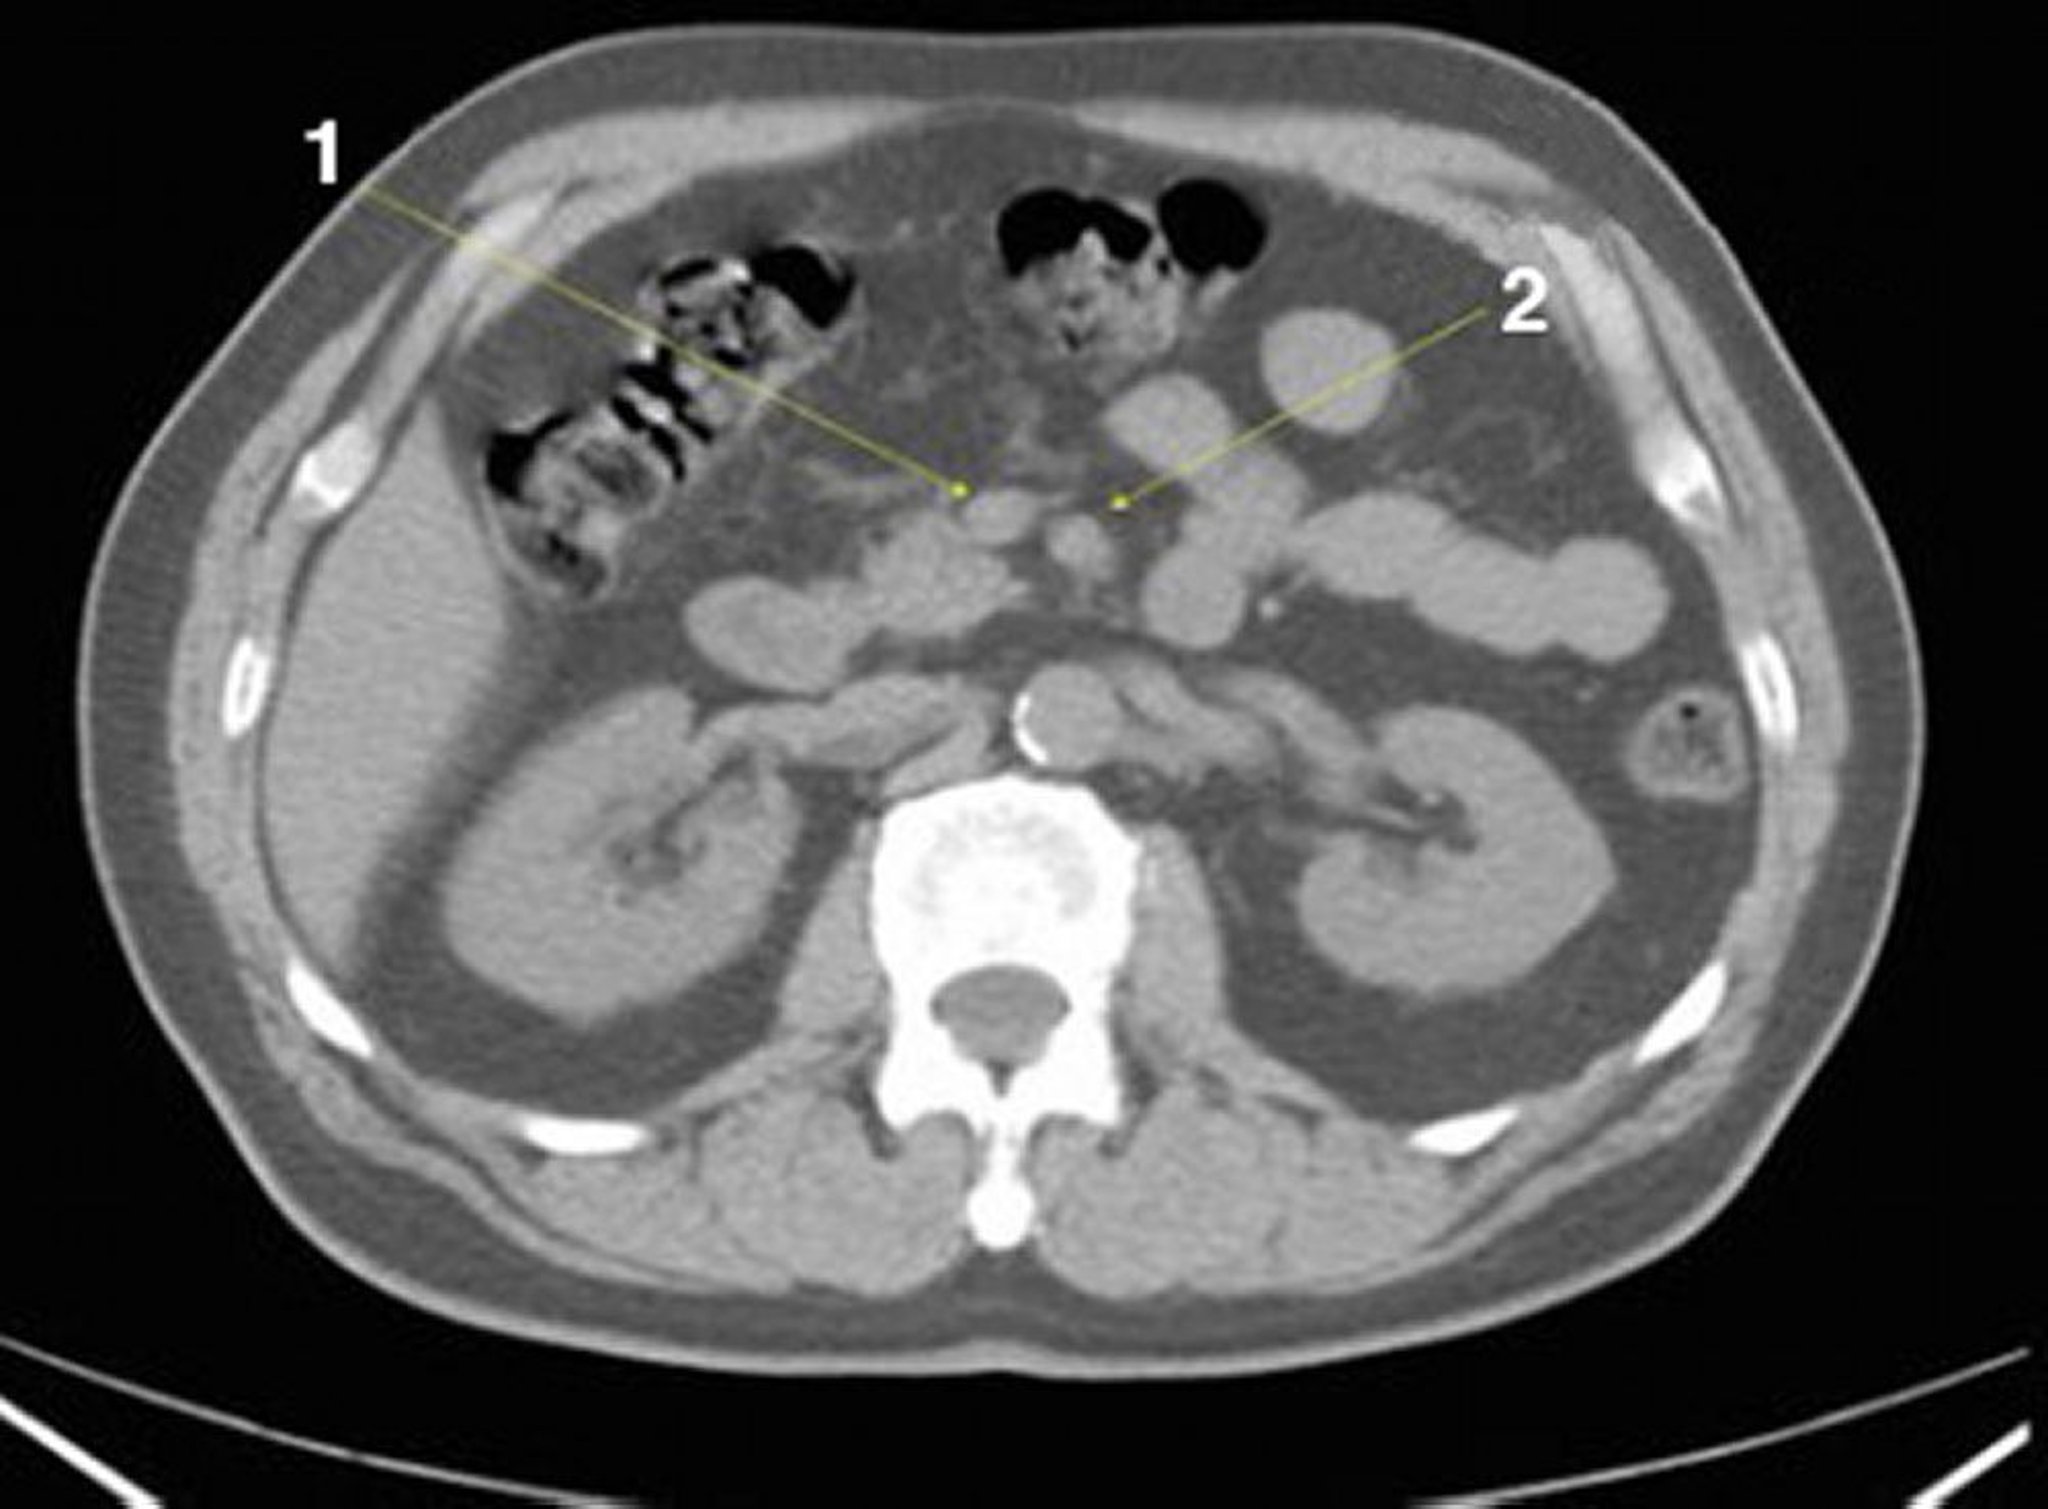

Tomografía computarizada sin contraste de abdomen y pelvis que muestra anatomía normal (corte 13)

1 = vena mesentérica superior; 2 = arteria mesentérica superior.